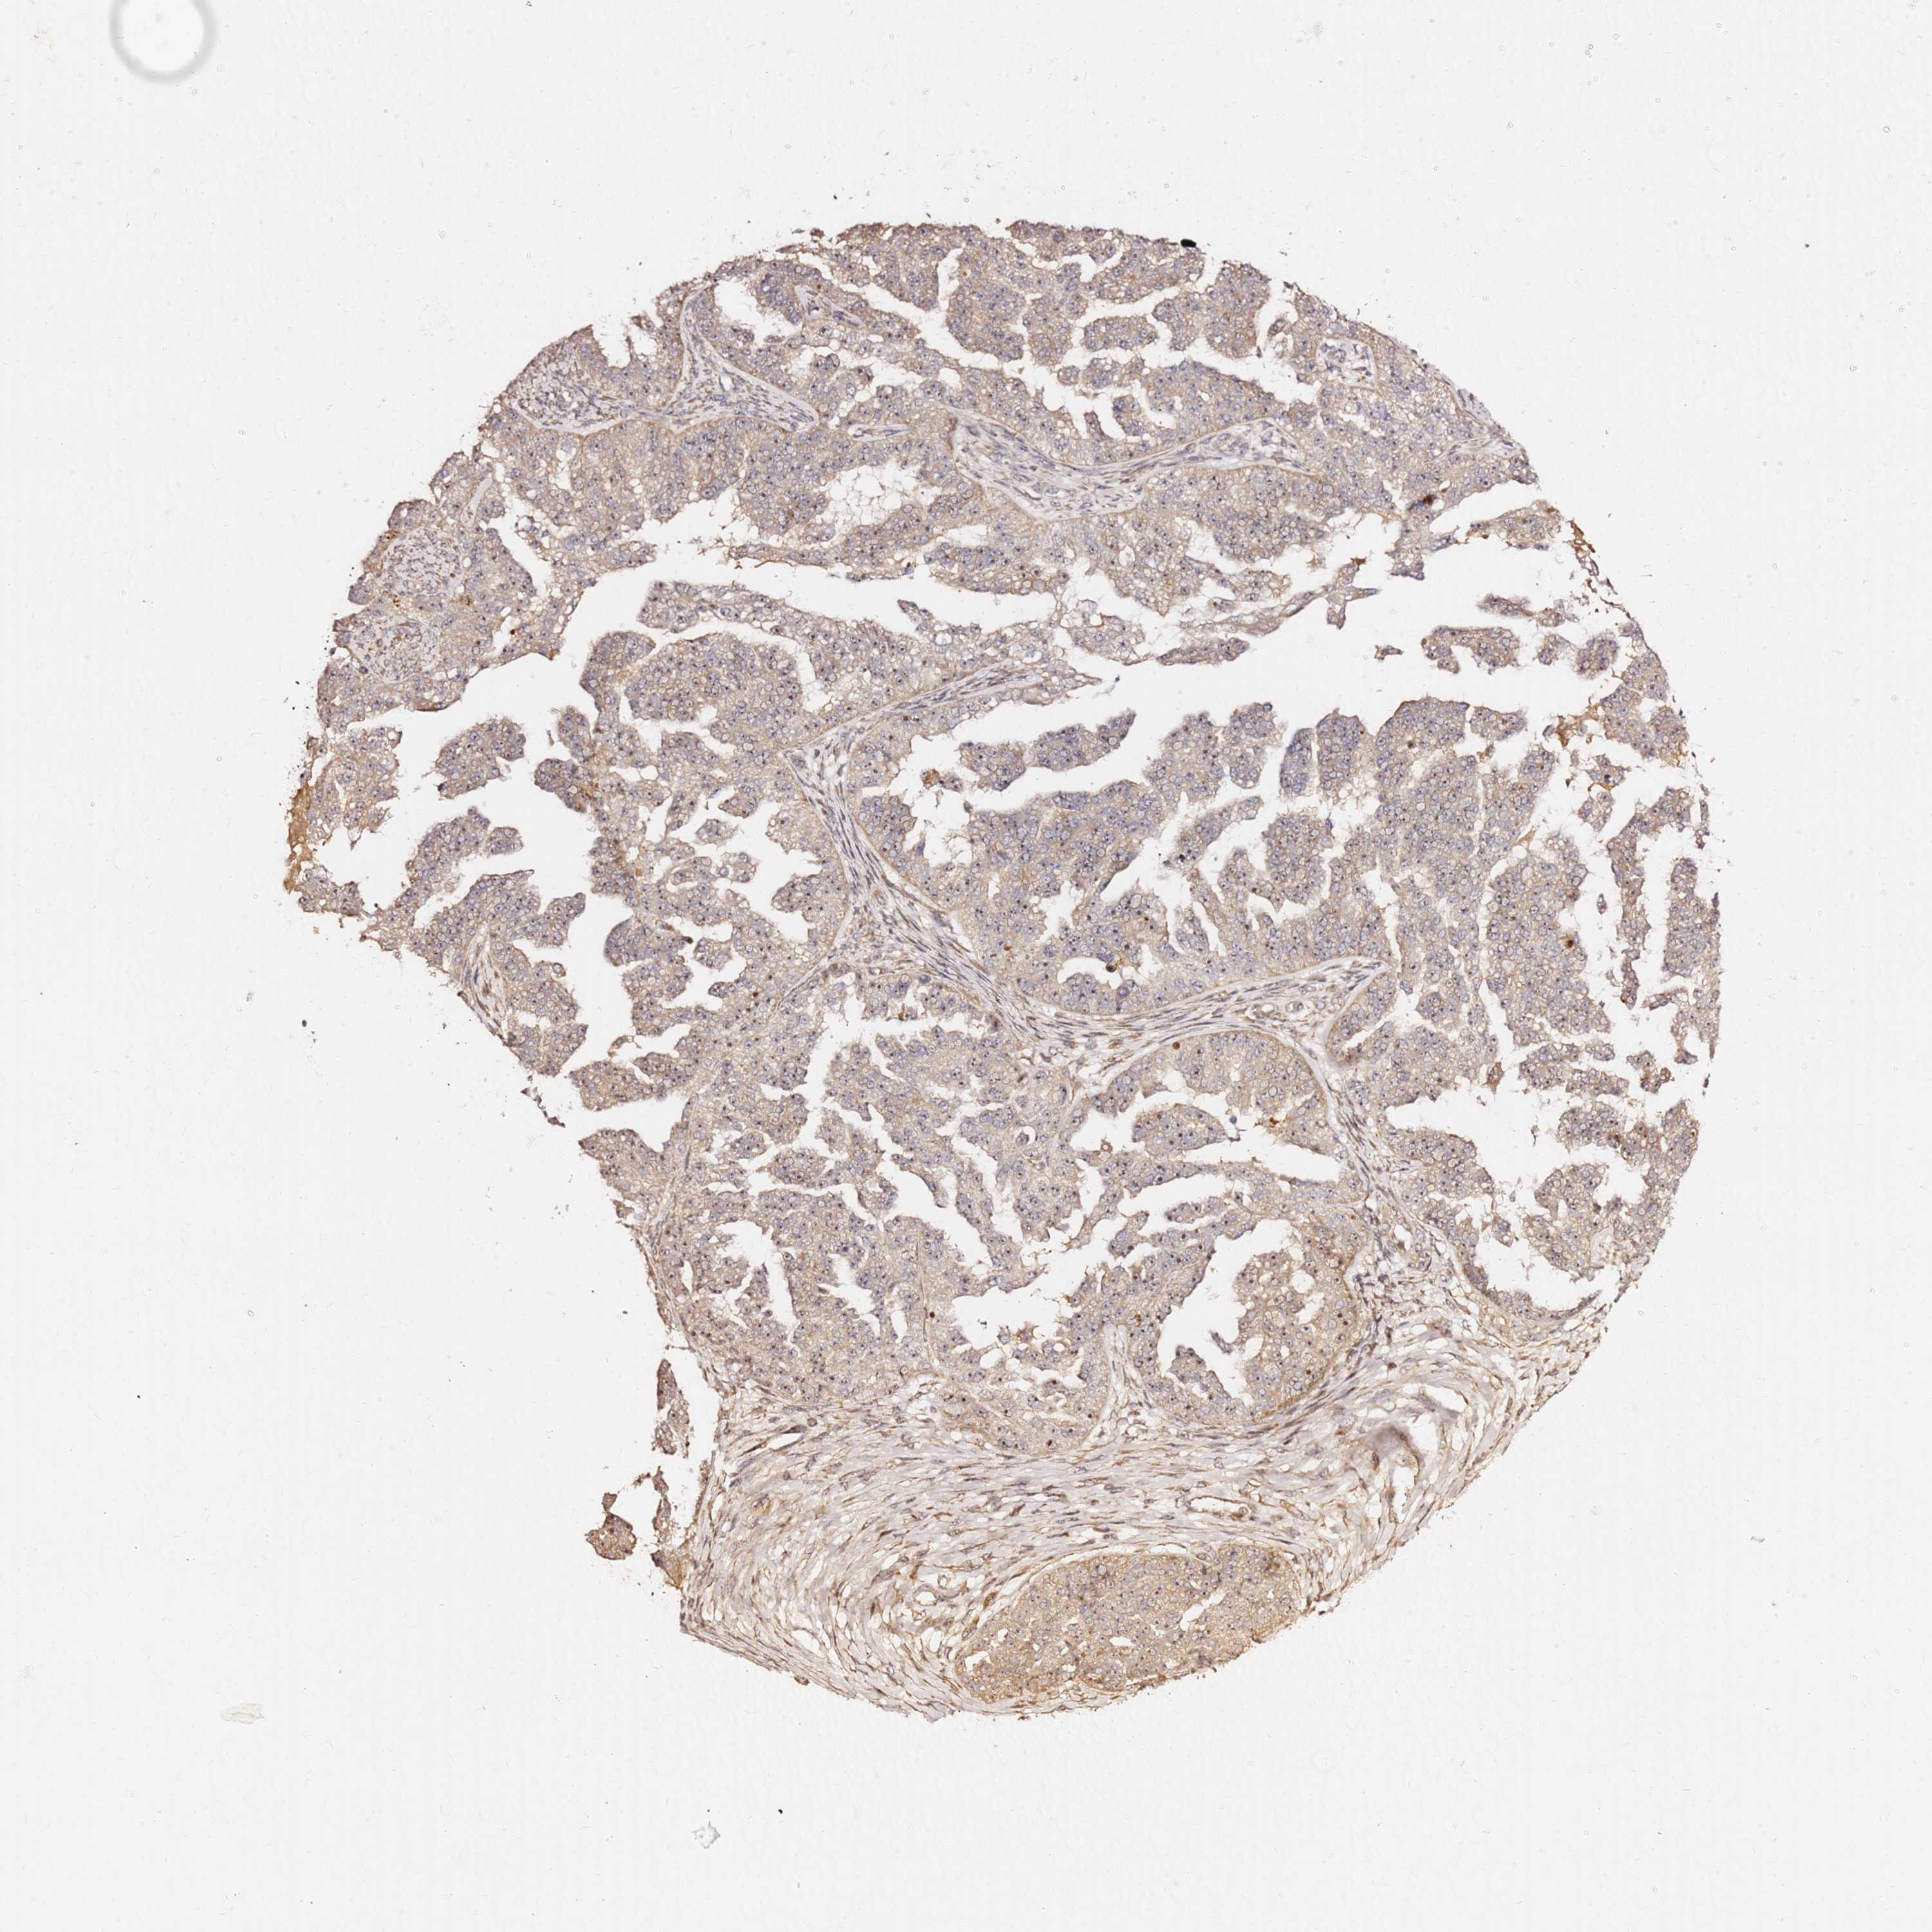

OVARIAN CANCER - Protein expressioni

A mouse-over function shows sample information and annotation data. Click on an image to view it in a full screen mode. Samples can be filtered based on level of antibody staining by selecting one or several of the following categories: high, medium, low and not detected. The assay and annotation is described here.

Note that samples used for immunohistochemistry by the Human Protein Atlas do not correspond to samples in the TCGA dataset.

Antibody stainingi

Antibody staining in the annotated cell types in the current human tissue is reported as not detected, low, medium, or high, based on conventional immunohistochemistry profiling in selected tissues. This score is based on the combination of the staining intensity and fraction of stained cells.

Each image is clickable and will lead to virtual microscopy that enables deeper exploration of all samples and also displays staining intensity scores, fraction scores and subcellular localization as well as patient and tissue information for each sample.

Antibody HPA046153

Staining

High

Medium

Low

Not detected

Intensity

Strong

Moderate

Weak

Negative

Quantity

>75%

75%-25%

<25%

None

Location

Nuclear

Cytoplasmic/membranous

Cytoplasmic/membranous,nuclear

Cystadenocarcinoma, serous, NOS

Carcinoma, endometroid

Cystadenocarcinoma, mucinous, NOS

Carcinoma, NOS